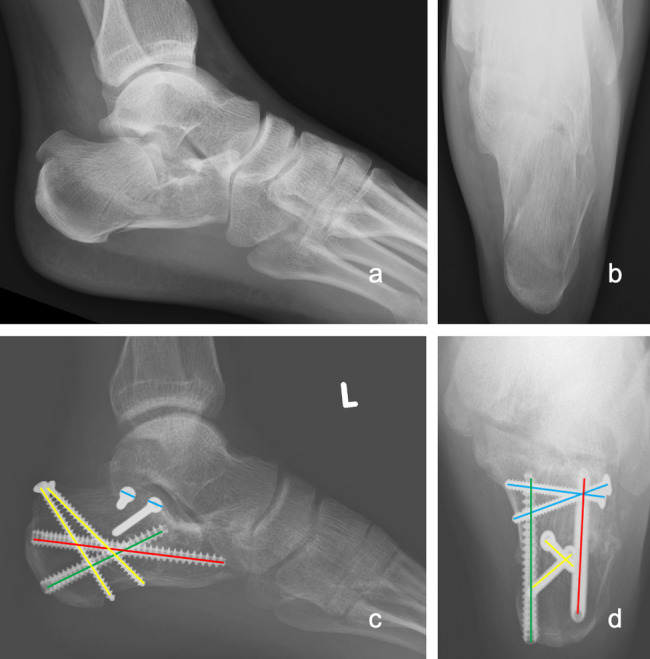

Methods: A total of 38 patients and 40 feet with DIACFs from 2015 to 2020 were retrospectively reviewed with a minimum of 3 years of follow-up. Patients were divided into two groups based on fixation method: minimally invasive locking plate fixation (MIP group) versus screw fixation (SW group) (17 vs 23, respectively). The clinical outcomes were evaluated by the Visual Analogue Scale (VAS), Maryland Foot Score (MFS), Olerud-Molander (OM) ankle score, American Orthopaedic Foot and Ankle Society (AOFAS) hindfoot score, and occurrence of complications. Radiological outcomes were assessed by radiographs for multiple parameters, including calcaneal height, length, width, and Böhler's angle.

Results: The patients were followed up for an average of 63.37 months. There was no significant difference in the final VAS score, MFS, OM score, AOFAS score, and the total incidence of complications between the two groups (P>0.05). Regarding the radiological outcome, there was also no significant difference in the reduction loss of calcaneal height, length, width, and Böhler's angle (P>0.05) after a one-year follow-up period. However, the rate of implant removal in the MIP group was significantly greater than that in the SW group (P< 0.05).

Conclusions: Minimally invasive locking plate fixation versus screw fixation of DIACFs via sinus tarsi approach may yield comparable radiological and functional outcomes. The screw fixation group suggested a shorter surgical time and lower implant removal rate. Both surgical methods are viable options for DIACFs. However, further large-scale prospective studies are warranted to confirm these results.